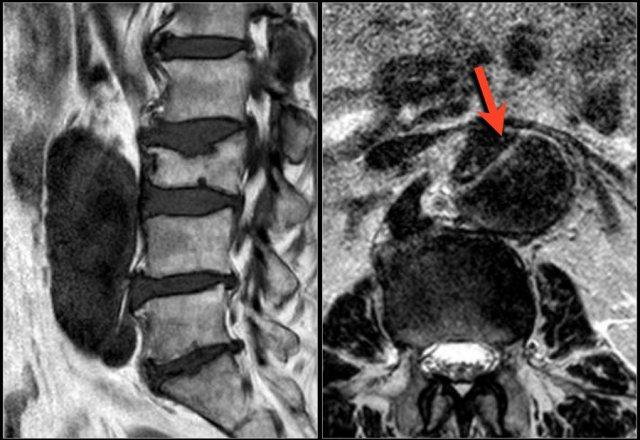

Hình ảnh lồi đĩa đệm khu trú tại mức L5S1.

Rễ thần kinh S1 bị chèn ép (mũi tên).

Hãy cuộn qua các hình ảnh và mô tả các dấu hiệu tìm thấy.

Sau đó tiếp tục đọc.

Các dấu hiệu tại các mức 1-4 như sau:

- Tại mức đĩa đệm, có hẹp ống sống tối thiểu do phình đĩa đệm và thoái hóa khớp mỏm khớp.

- Tại mức này, có hẹp ống sống nặng do phình đĩa đệm và thoái hóa khớp mỏm khớp.

Ngoài ra còn có rách vòng sợi (tăng tín hiệu) là nơi đĩa đệm thoát vị qua (mũi tên vàng). - Tại mức ngách bên, có thoát vị khu trú của chất đĩa đệm gây chèn ép rễ thần kinh L5 (mũi tên vàng).

Đây được gọi là thoát vị thực sự (extrusion), vì khoảng cách giữa các bờ của khối thoát vị lớn hơn khoảng cách tại nền. - Rễ thần kinh L5 bị chèn ép (mũi tên xanh dương) trong ngách bên.

Đĩa đệm thoát vị đã di trú xuống phía dưới và được thấy như một cấu trúc hình bầu dục nằm phía trước rễ thần kinh.

Đĩa đệm thoát vị không được bao bọc, tức là không được che phủ bởi các sợi của vòng sợi.